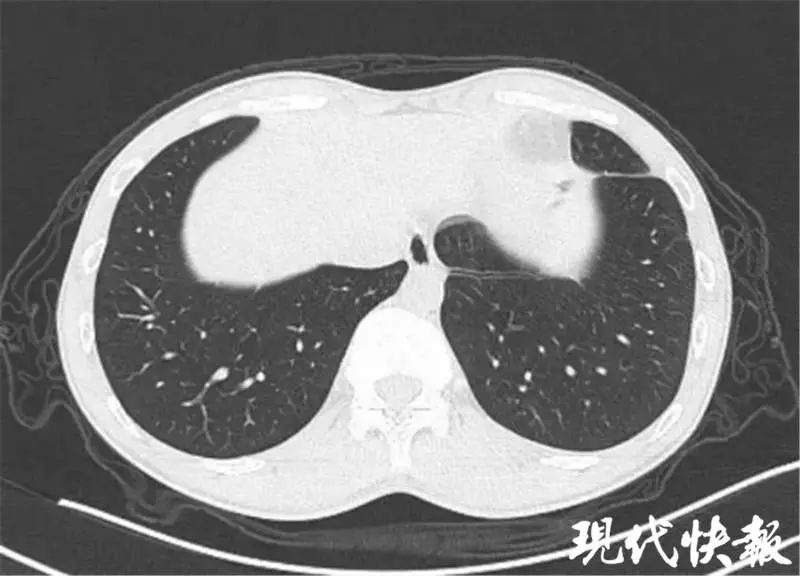

医生反复诊断,发现竟是……_肺吸虫